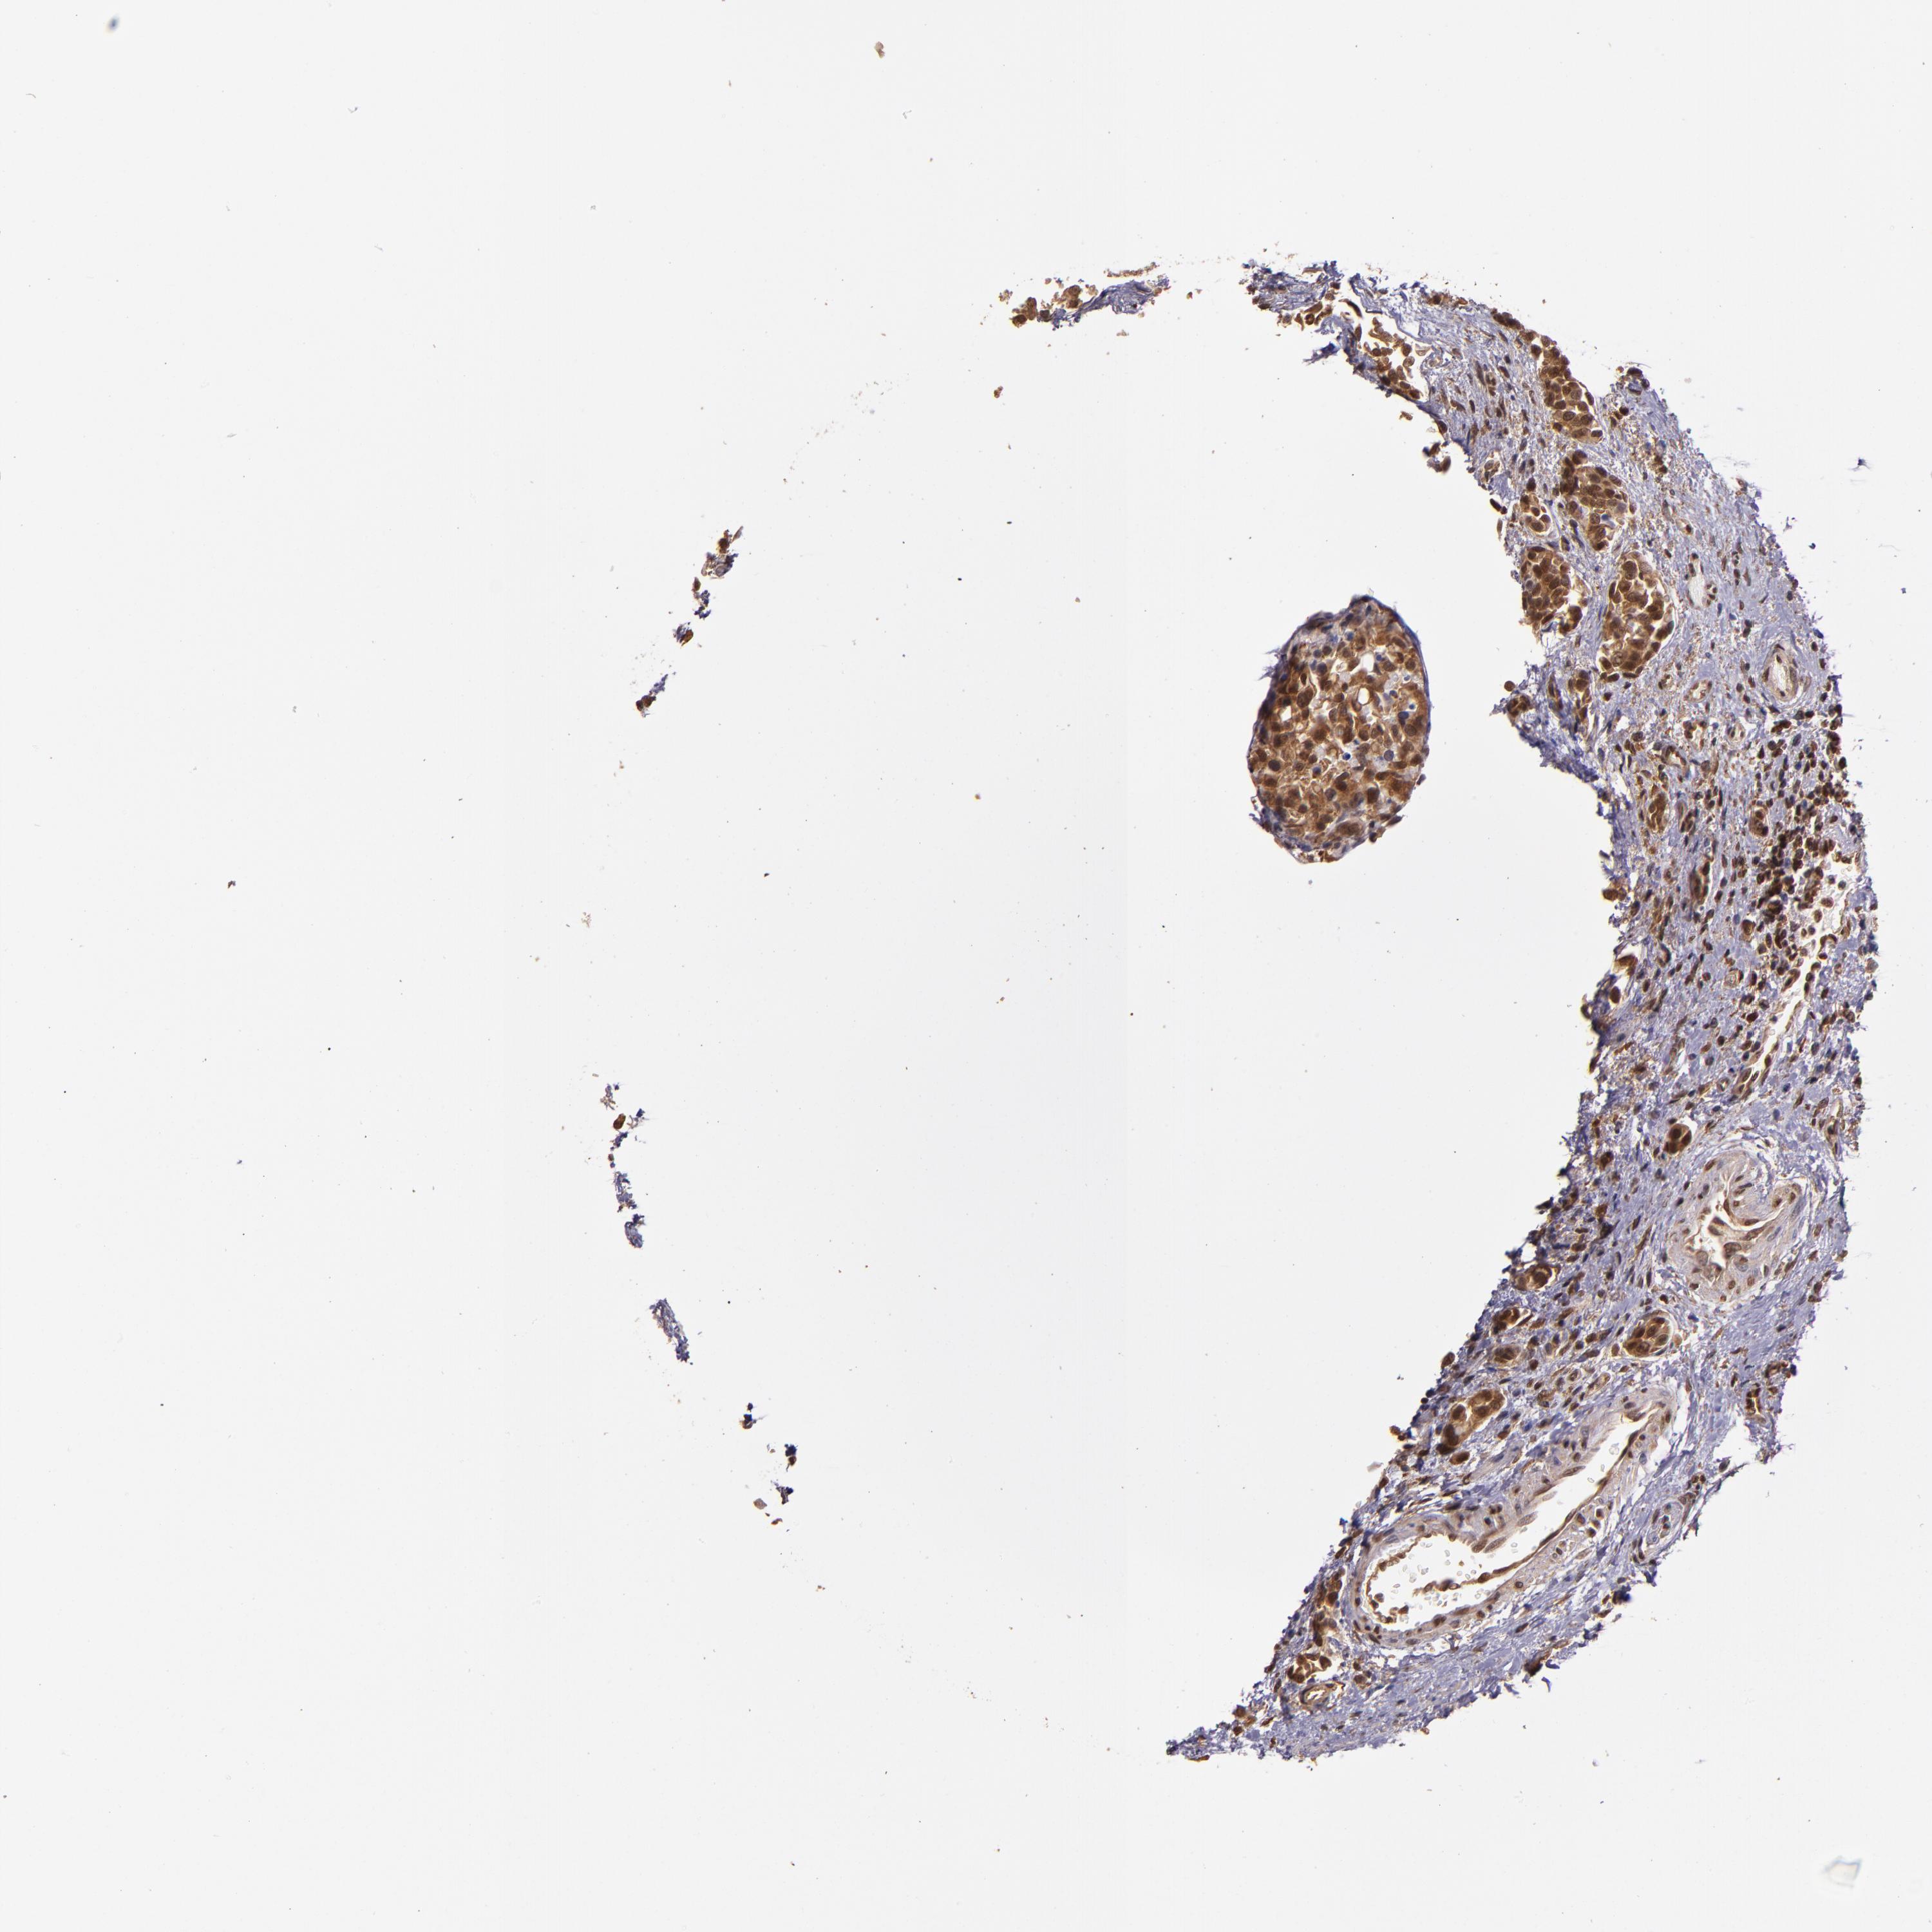

UROTHELIAL CANCER - Protein expressioni

A mouse-over function shows sample information and annotation data. Click on an image to view it in a full screen mode. Samples can be filtered based on level of antibody staining by selecting one or several of the following categories: high, medium, low and not detected. The assay and annotation is described here.

Antibody stainingi

Antibody staining in the annotated cell types in the current human tissue is reported as not detected, low, medium, or high, based on conventional immunohistochemistry profiling in selected tissues. This score is based on the combination of the staining intensity and fraction of stained cells.

Each image is clickable and will lead to virtual microscopy that enables deeper exploration of all samples and also displays staining intensity scores, fraction scores and subcellular localization as well as patient and tissue information for each sample.

Antibody HPA001861

Staining

High

Medium

Low

Not detected

Intensity

Strong

Moderate

Weak

Negative

Quantity

>75%

75%-25%

<25%

None

Location

Nuclear

Cytoplasmic/membranous

Cytoplasmic/membranous,nuclear

Urothelial carcinoma, High grade

Urothelial carcinoma, Low grade